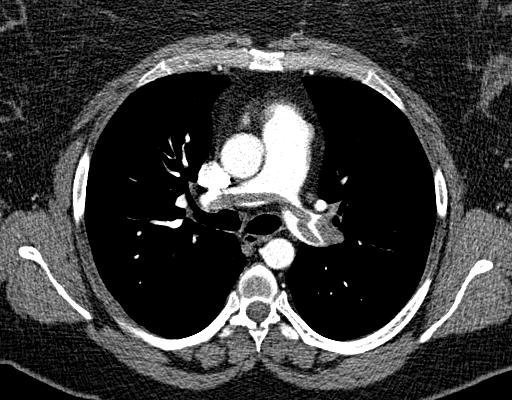

Filling defects in right PA, RV dilation (RV/LV 1.3), septal bowing โ saddle PE